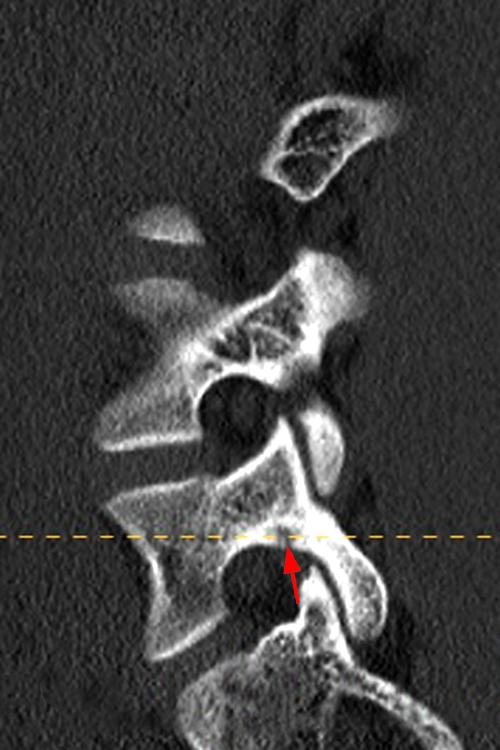

Case 1: T2-weighted axial (3A) and sagittal STIR (3B) sequences show marked cortical T2/STIR hyperintensity in the left pedicle of L5 surrounding a hypointense line (arrows) which begins at the inferior/medial margin of the pedicle and nearly completely traverses the pedicle.

Case 1: Acute left-sided pediculolysis